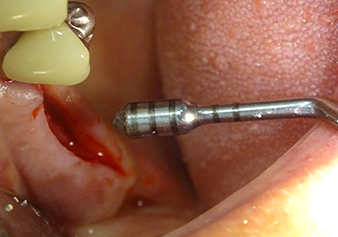

The Schneiderian membrane is carefully detached with the Z25P instrument (phase 1)

Fig.3: Following marking of the implant position and initial expansion of the bed, the Schneiderian membrane is carefully detached with the Z25P instrument (phase 1).

The I2A instrument (diameter 2.0 mm) was then used to perforate the sinus floor intermittently and on the smallest scale possible. This special piezosurgical method ensures that the Schneiderian membrane is not damaged. When the Z25P was used, the membrane was already lifted slightly by the coolant supplied via the instrument tip (Fig. 3). The coolant quantity was just 50% in order to avoid high pressure in the implant bed.